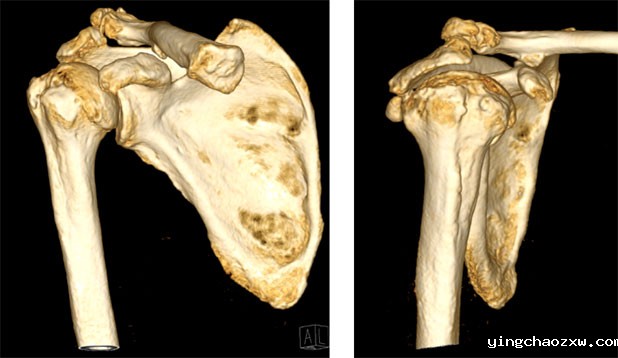

2.术前X片和CT提示严重的肩关节骨关节病。